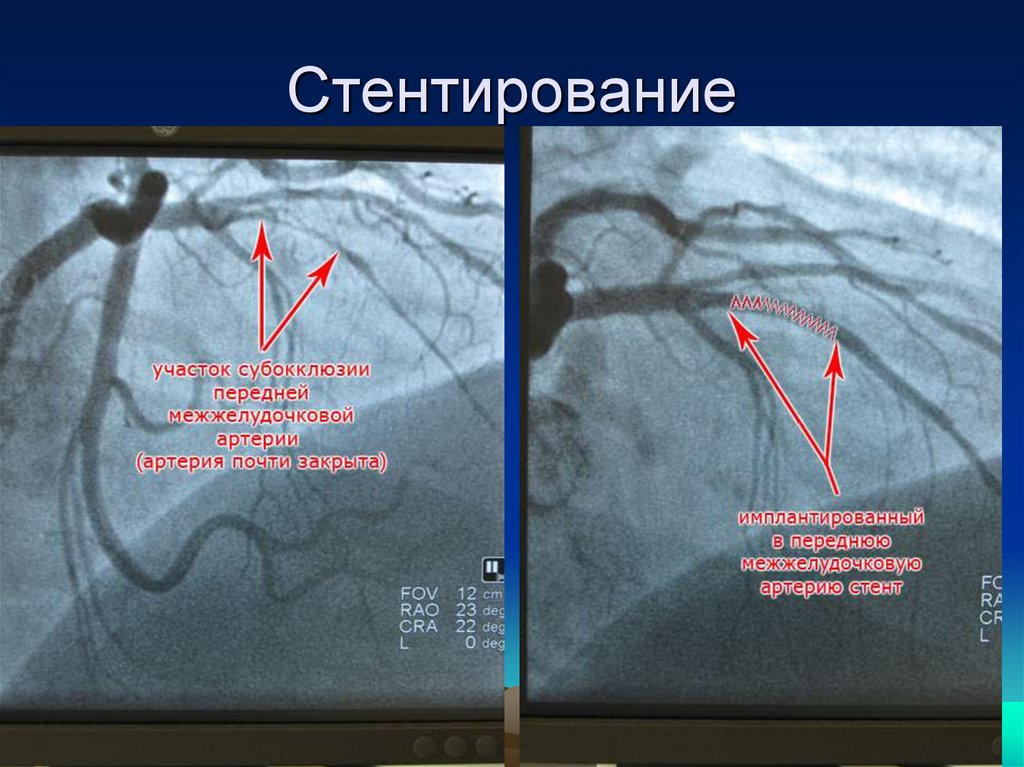

Стентирование сердца форум. Стентирование сердца форум. Стентирование сердца форум. Баллонная ангиопластика коронарных артерий. Коронографияистэнтирование.

Инфаркт миокарда стентирование. Стентирование сердца форум. Стентирование сердца форум. Операция на сердце коронарография и стентирование. Коронарография сердца стентирование.

Стентирование коронарных артерий. Стентирование зжмж пка. Стентирование топографическая анатомия. Операция на сердце коронарография и стентирование. Стентирование сердца форум.

Стентирование позвоночной артерии. Что такое стентирование пмжв лка. Операция на сердце стентирование. Стентирование коронарных артерий. Чкв баллонная ангиопластика.

Перевал дятлова стентирование сосудов сердца. Стентирование коронарных артерий. Операция стентирование сосудов сердца. Стентирование ствола лка. Стентирование коронарных артерий.